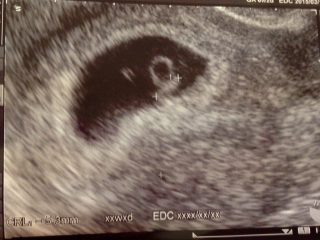

「妊娠超初期」とは妊娠が判明する前の妊娠0ー3週頃のことを指します。

妊娠超初期は生理予定日の1週間前に起こるとされていますが、いつからはじまるのでしょうか?それを知るには、まず排卵から着床するまでの流れを知る必要があります。

受精卵が着床して、はじめて妊娠超初期に入り、症状を感じはじめる方が多いです。つまり、妊娠超初期症状は着床したときにはじまります。